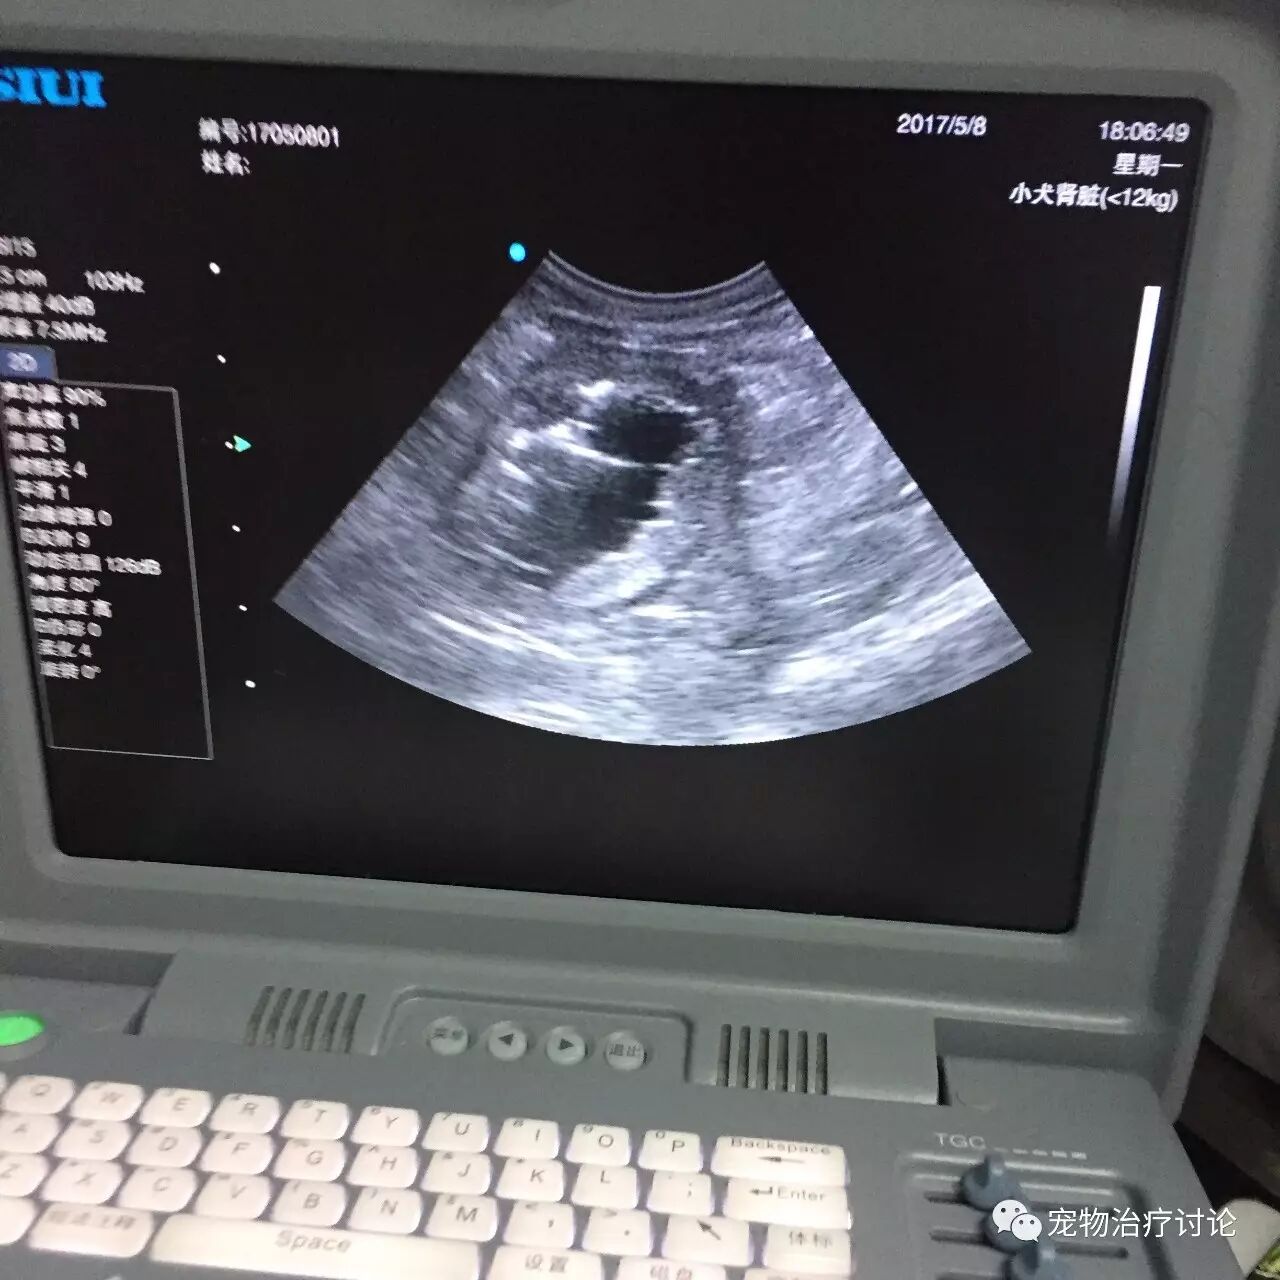

㈢、X线及B超诊断

2、检查是否有阳性结石。

3、有时需要结合造影检查膀胱壁的损伤情况。

4、检查肾脏的大小。

6、通过B超诊断查看是否有肿瘤。